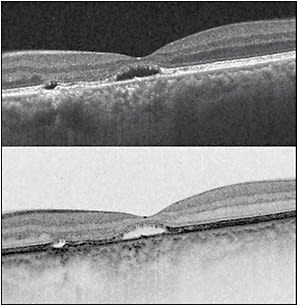

Central serous chorioretinopathy (CSC) is characterized by distorted vision (micropsia, metamorphopsia, reduced contrast sensitivity, color desaturation) due to a serous detachment of the neurosensory retina associated with leakage at the (usually impermeable) tight junctions between adjacent retinal pigment epithelial (RPE) cells. The region of exudative retinal detachment in CSC usually occurs in the region of highest choroidal circulation, in the posterior pole of the eye, therefore affecting the central visual field. Spectral-domain optical coherence tomography (SD-OCT) in patients with active CSC typically shows an elevated neurosensory retina above the RPE, which itself is often focally detached over Bruch’s membrane.

The natural history in the vast majority of CSC cases is spontaneous resolution within 2-3 months (so-called classic CSC). In these cases, central vision is minimally affected and usually returns to normal after reabsorption of the subretinal fluid (Figure 1). However, as many as 10% of all patients with CSC develop persistent serous macular detachment (chronic CSC or “diffuse retinal pigment epitheliopathy” [DRPE], lasting 3 months to 6 months or longer).10 In these DRPE cases, progressive and irreversible visual decline can be associated with the development of central RPE atrophy and (due to increased diffusion distance between the oxygenating and nourishing choriocapillaris, trophic RPE, and the photoreceptors) cystoid macular degeneration and foveal atrophy (Figures 2 and 3).11-15

In patients with CSC, it is frequently difficult to discern the exact duration of the episode, so it is prudent to follow the patient’s OCT — specifically the layers indicating photoreceptor integrity: the ELM and the EZ — for disruption or granulation. Treatment prior to photoreceptor disruption would prevent vision loss.

Based on these observations, a reasonable approach to the patient with CSC would be monthly follow-up with serial OCT; active treatment should be considered after a CSC episode duration of 3 months. The exact duration of the episode is often impossible to determine, so a conservative approach would include a generous estimate of the duration and prompt initiation of active treatment if disruption of the EZ occurs (disruption of the EZ occurs before ELM disruption).24-26